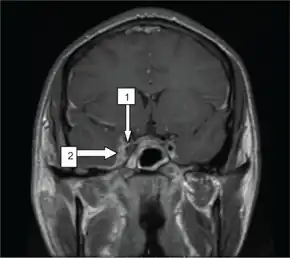

Sinus films are helpful in the diagnosis of sphenoid sinusitis. Opacification, sclerosis, and air-fluid levels are typical findings. Contrast-enhanced CT scan may reveal underlying sinusitis, thickening of the superior ophthalmic vein, and irregular filling defects within the cavernous sinus; however, findings may be normal early in the disease course. An MRI using flow parameters and an MR venogram are more sensitive than a CT scan and are the imaging studies of choice to diagnose cavernous sinus thrombosis. Findings may include deformity of the internal carotid artery within the cavernous sinus, and an obvious signal hyperintensity within thrombosed vascular sinuses on all pulse sequences.Cerebral angiography can be performed, but it is invasive and not very sensitive. Orbital venography is difficult to perform, but it is excellent in diagnosing occlusion of the cavernous sinus.[11]